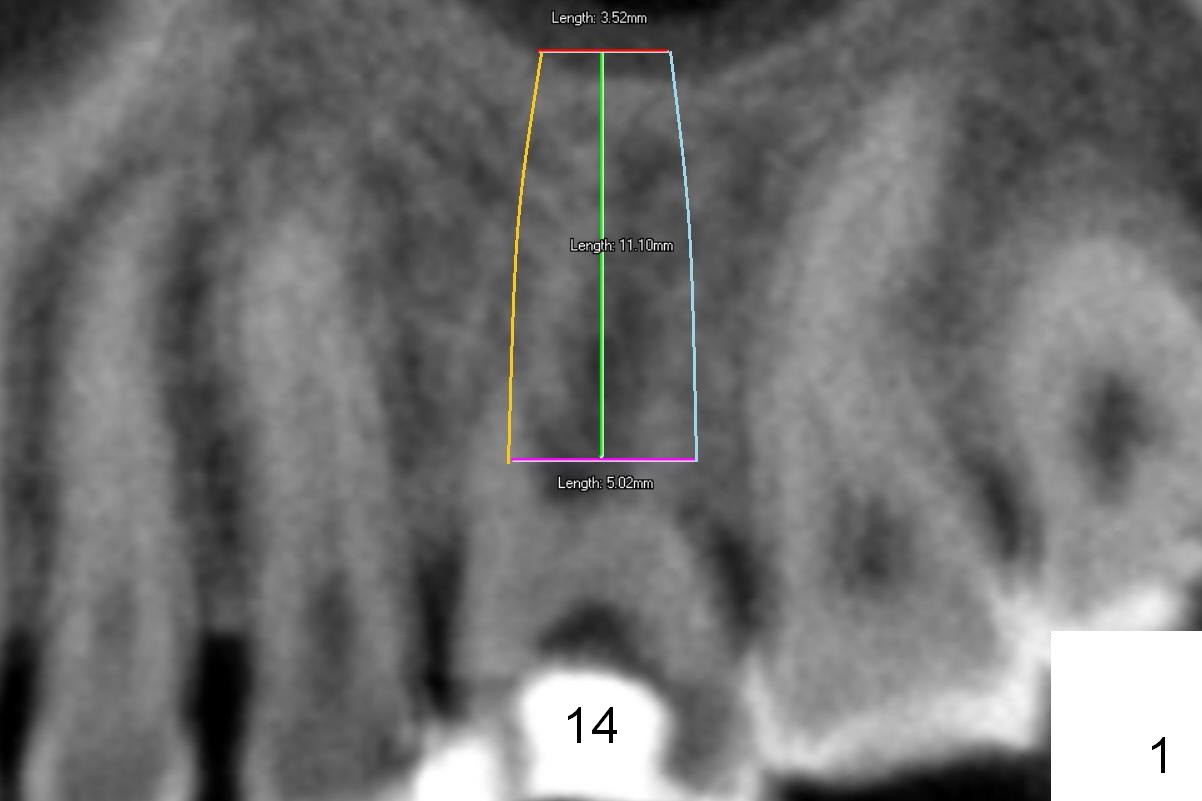

Preop CT shows that the septum appears to be able to hold a 11 mm long implant (Fig.1 sagittal section). There are periapical radiolucent lesions of the buccal (Fig.2 (coronal section) B) and palatal roots; bone height above the buccal apex is ~ 2 mm (Fig.3). When the tooth #14 is extracted, a 1.6 mm pilot drill is used to start osteotomy in the middle of the fairly thin septum (Fig.3 red line, Fig.4 S). It is hoped that Magic Expanders (ME) can enlarge the osteotomy by pushing the buccal and palatal bone plates of the septum outward (Fig.5 arrows).